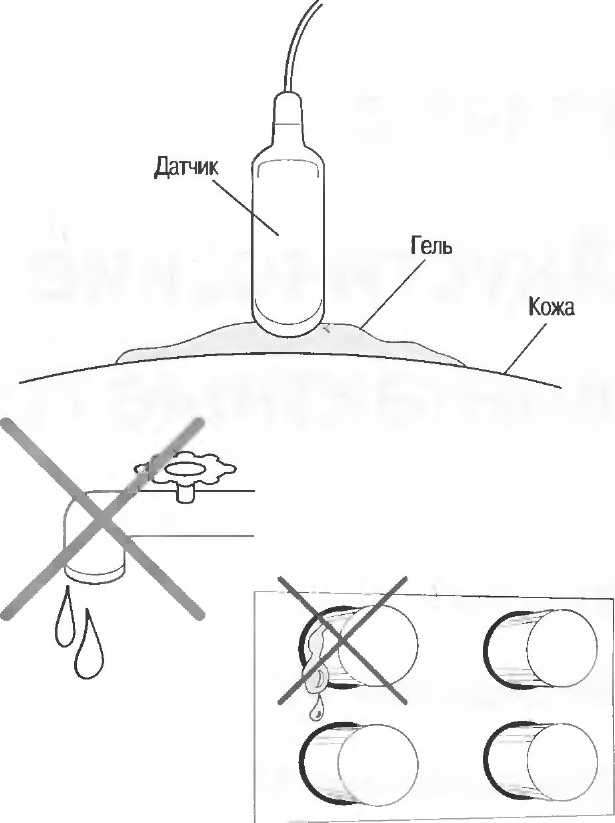

Связьшающий агент (контактный гель) |

Жидкость или гель, используемые для заполнения пространства между датчиком и поверхностью кожи таким образом, чтобы не оставалось воздушной прослойки, мешающей прохождению ультразвука. |

В результате наличия раздела сред для ультразвукового исследования необходим акустический гель, связывающий поверхность кожи и датчик, для того чтобы воздух не препятствовал распространению ультразвуковых волн.

Контакт с кожей пациента

Датчик должен перемещаться по телу пациента; для этого кожа пациента в области, где проводится исследование, должна быть всегда покрыта контактным гелем для лучшего проведения ультразвуковой волны и облегчения движения датчика.

При перемещении датчика по коже пациента он должен находиться в тесном контакте с кожей через контактный гель; движение должно быть постоянным и последовательным, по мере того как оператор тщательно анализирует получаемое изображение на экране.

Если при проведении исследования воздух проникает между датчиком и кожей пациента, он становится барьером, отражающим все ультразвуковые сигналы, препятствуя их проникновению к тканям пациента. Для получения качественного изображения необходимо использовать жидкую среду для связи между датчиком и поверхностью тела пациента. Эта жидкость называется акустическим связывающим агентом и часто обозначается как «гель».

Вода не является хорошим связывающим агентом, так как она очень быстро испаряется с горячего тела пациента: она также стекает с тела пациента при движении датчика. Воду можно использовать только в экстренной ситуации, когда ничего другого нет под рукой.

Масло, минеральное или растительное, является хорошим связывающим агентом, но при длительном использовании оно может растворять резиновое или пластиковое покрытие оборудования. Если масло попадает на пальцы оператора, как это обычно и происходит, то это может повредить контрольным устройствам аппарата.

Лучшими акустическими связывающими агентами являются водорастворимые гели. Многие из них производятся промышленным путем, но они стоят дорого, их временами трудно получить. Нет необходимости использования специального связывающего агента для отдельного вида оборудования, даже если производители настаивают на этом. Специальные связывающие агенты не дают преимущества в получении изображения. Формула связывающего агента для аппаратуры общего назначения для любого датчика приведена на с. 45.

Связывающий агент лучше использовать в пластиковых бутылочках, из которых гель выдавливается на кожу пациента. Это позволяет избежать излишнего загрязнения. Пригодна любая пластиковая сжимаемая бутылочка, но она должна быть полностью чистой и сухой перед тем, как будет заполнена гелем. Если имеется открытая рана, повреждение кожи или другой риск инфицирования, покройте датчик или кожу пластиком; поместите связывающий агент по обе стороны пластика. Датчик необходимо очищать после каждого пациента.

Связывающий агент может быть удален с помощью салфетки, бумажных или матерчатых полотенец. Его нужно полностью удалить во избежание загрязнения одежды пациента.

Запомните: если изображение нечеткое или общая чувствительность снижена, не надо регулировать чувствительность, пока не добавите гель на кожу пациента.

Никогда не бывает слишком много геля.